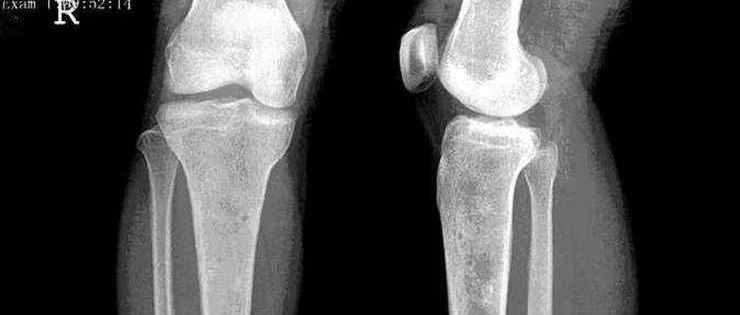

点击标题下「蓝色微信名」可快速关注文章来源: 中华骨科杂志,2020,40 (15): 979-987作者:孙昆昆 谢璐 郭卫 孙亦雯 孔方舟 沈丹华摘要 目的探讨透明细胞软骨肉瘤(clear cell chondrosarcoma,CCCS)的临床表现、影像学特点、病理组织学特征、诊断陷阱、治疗以及预后。方法回顾性分析2010年1月至2020年1月23例收治并手术治疗的透明细胞软骨肉瘤患者资料,其中男21例,女2例;年龄(45.78±16.19)岁(范围:27~72岁)。21~40岁8例(35%),41~60岁10例(43%),61~80岁者5例(23%)。发病部位股骨8例,骨盆7例,胸腰椎4例,骶骨3例,胫骨1例。术前穿刺及术后大体标本用10%中性福尔马林固定,5%硝酸脱钙处理,石蜡包埋,行苏木素-伊红(hematoxylin and eosin,HE)染色及免疫组织化学染色(envision法),收集术前影像学表现及临床症状,术后显微镜下病理组织学表现及免疫表型,归纳总结透明细胞软骨肉瘤的临床、影像学及病理形态学特点。...